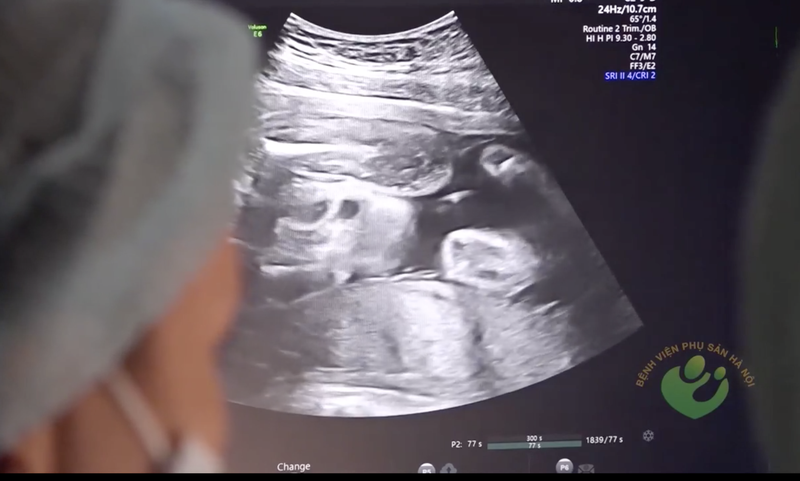

![]() |

Bác sĩ quan sát hình ảnh siêu âm thai nhi của sản phụ (Ảnh: BVCC) |